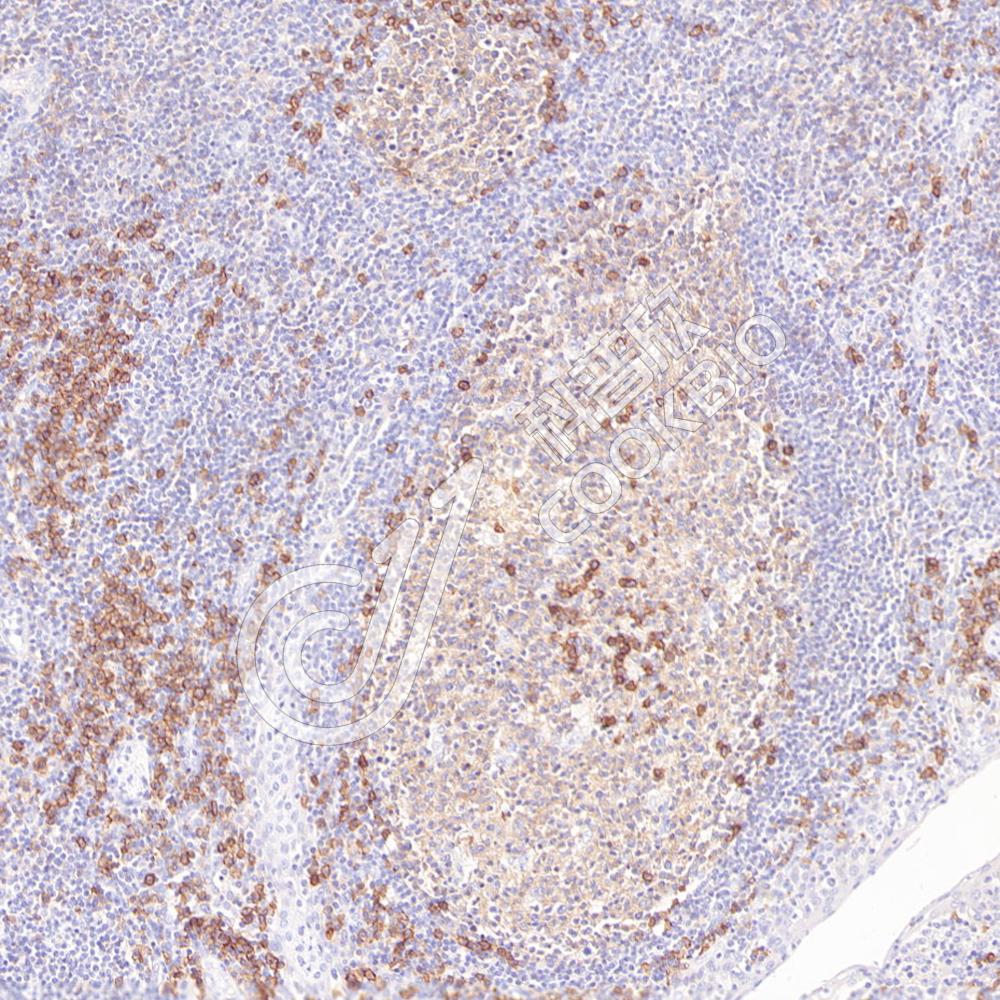

IHC检测CD38蛋白(货号 K1344493).

样品: 人扁桃体, 4%多聚甲醛 (货号KSG1101) 固定12-24小时.

抗原修复: 柠檬酸抗原修复液(干粉, pH 6.0) (KSG1201), 98℃, 20分钟.

—抗: 1: 1500稀释, 4℃ 孵育过夜.

二抗: S-vision免疫组化多聚二抗(山羊抗兔),即用型 (货号KB3906), 室温孵育20分钟.